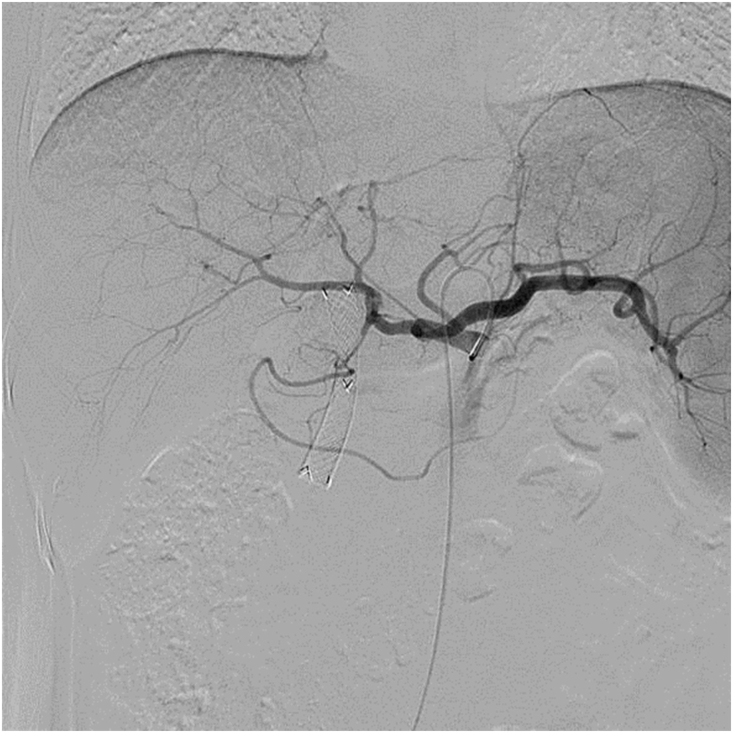

All TAI procedures were considered successful (total 85 times), withan average of 4.25 ± 1.55 procedures per patient. The treatment regimen involved 3 procedures in 10 cases, 4 procedures in 2 cases, 5 procedures in 2 cases, 7 procedures in 1 case and 8 procedures in 1 case. Five of the nine patients who did not undergo surgical resection showed a flaky, pancreatic area that showed lighter staining on superior mesenteric artery angiography (Fig. 1, Fig. 2). The remaining 15 patients showed no significant tumor staining (Fig. 3, Fig. 4).

Fig. 1.

Carcinoma staining at the head of the pancreas when angiographyat is performed at the opening of the celiac artery.